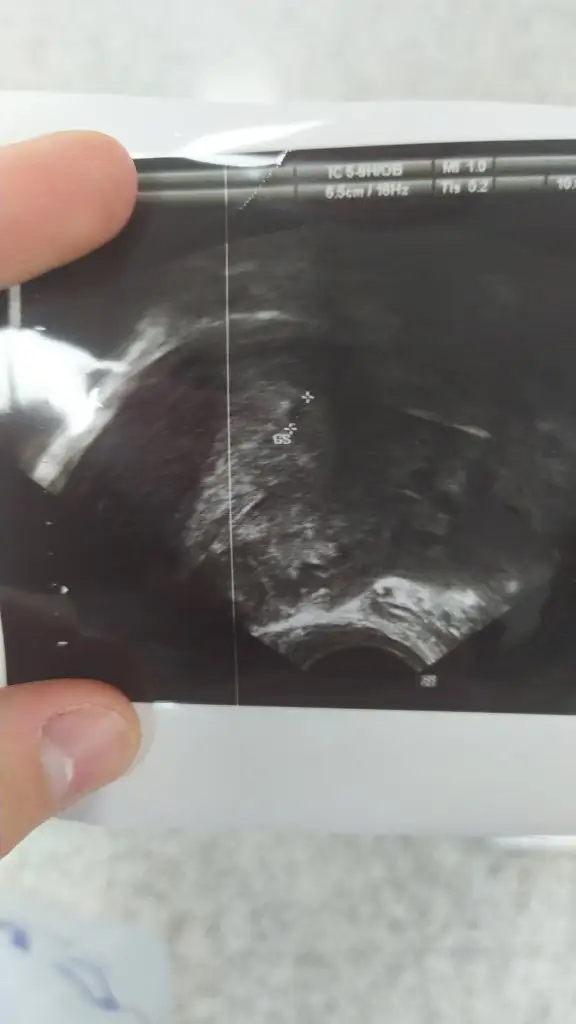

Yaa çok sevindim canım hayırlı uğurlu olsun tekrardanTeyzoslari bugün kesemizi gördük :) ama doktor bı emin olamadi en son pazartesi kan verdiğim de 113 çıkmıştı şuan gozukmemesi lazım nasıl gözüktü böyle dedi şaşırdı. Kan verdim tekrar gidicem bakalım ama yeri çok iyi dis gebelik ya da sezeryan yerine yerleşme gibi bı durum yok dedi. 5+2 şuan bakalım tekrar gidicem inşallah yanlış bişey yoktur